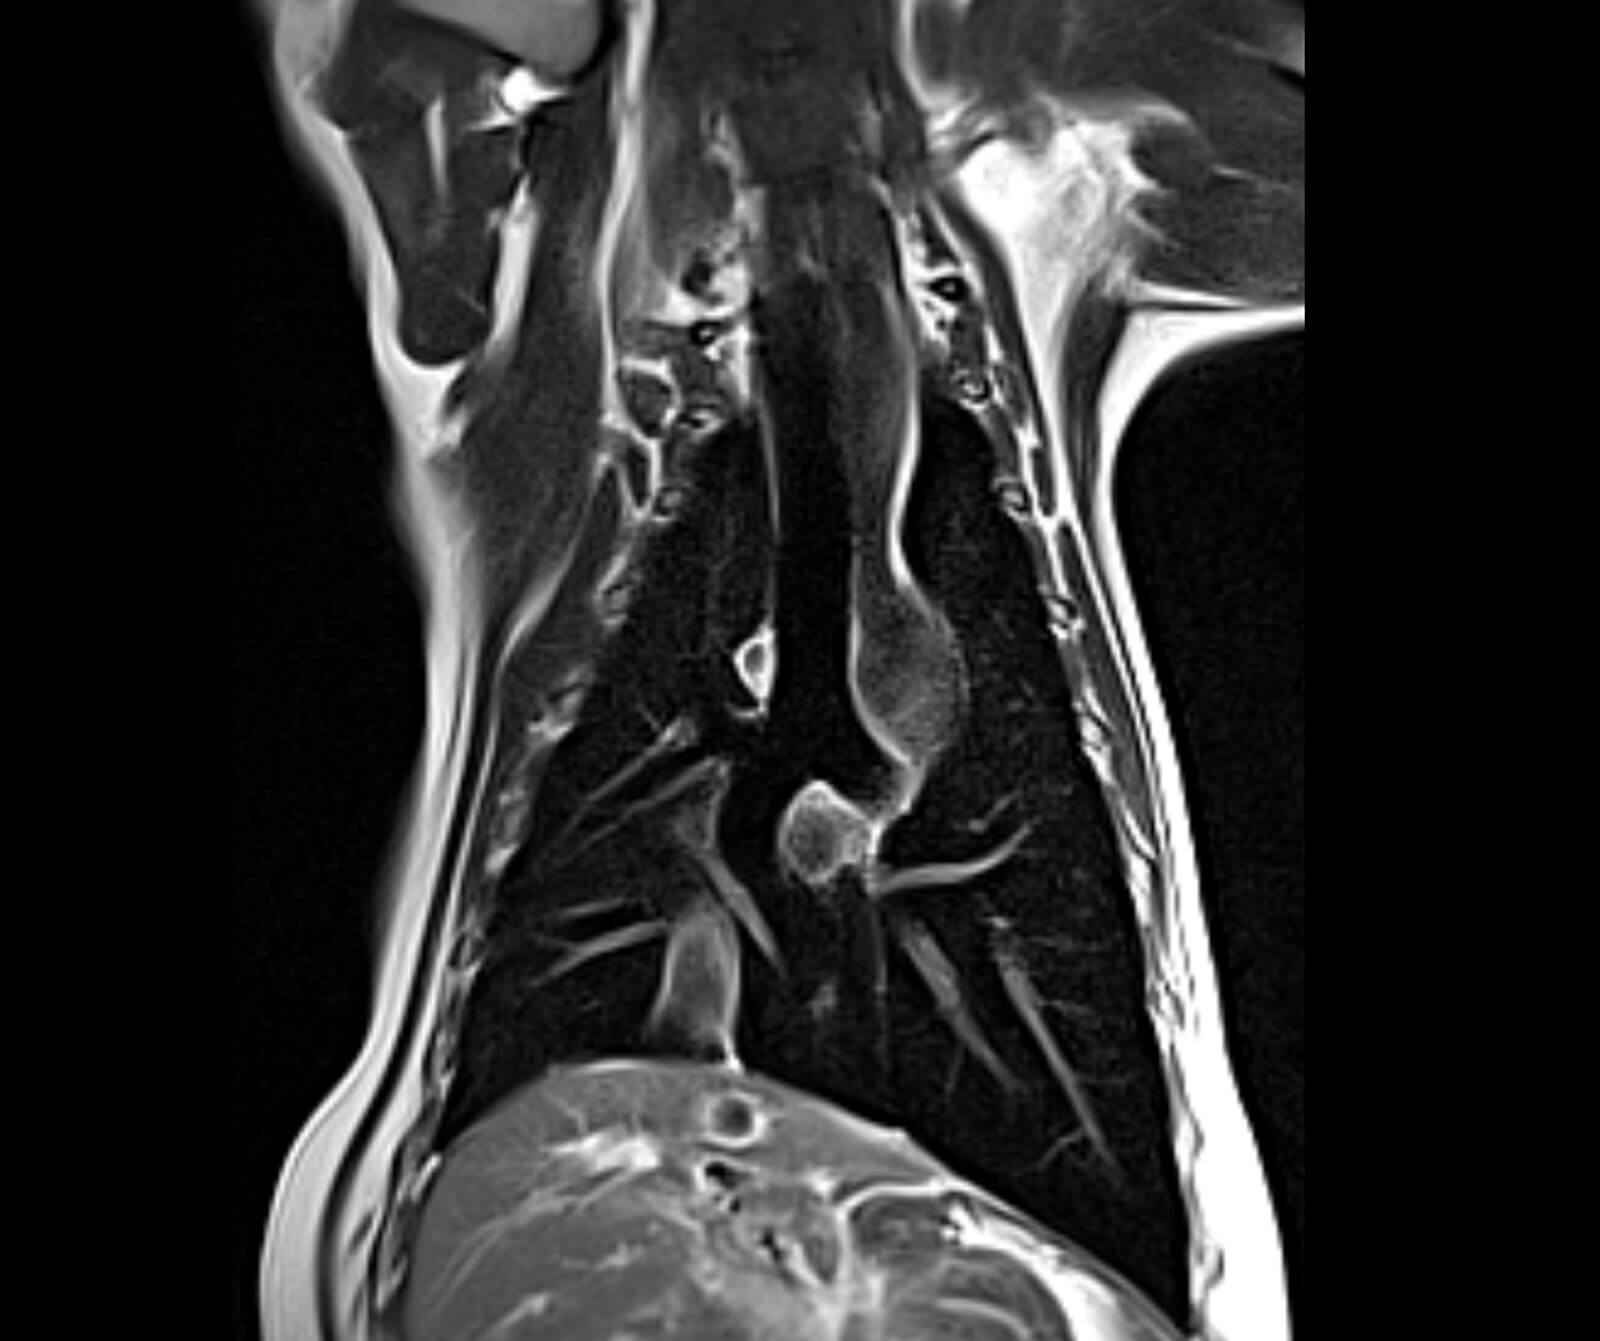

• Spinal kord incelemeleri

• Disk hernisi, omurga tümörleri, enfeksiyonlar ve spinal stenoz

• Omurilikte travmatik ve dejeneratif değişiklikler